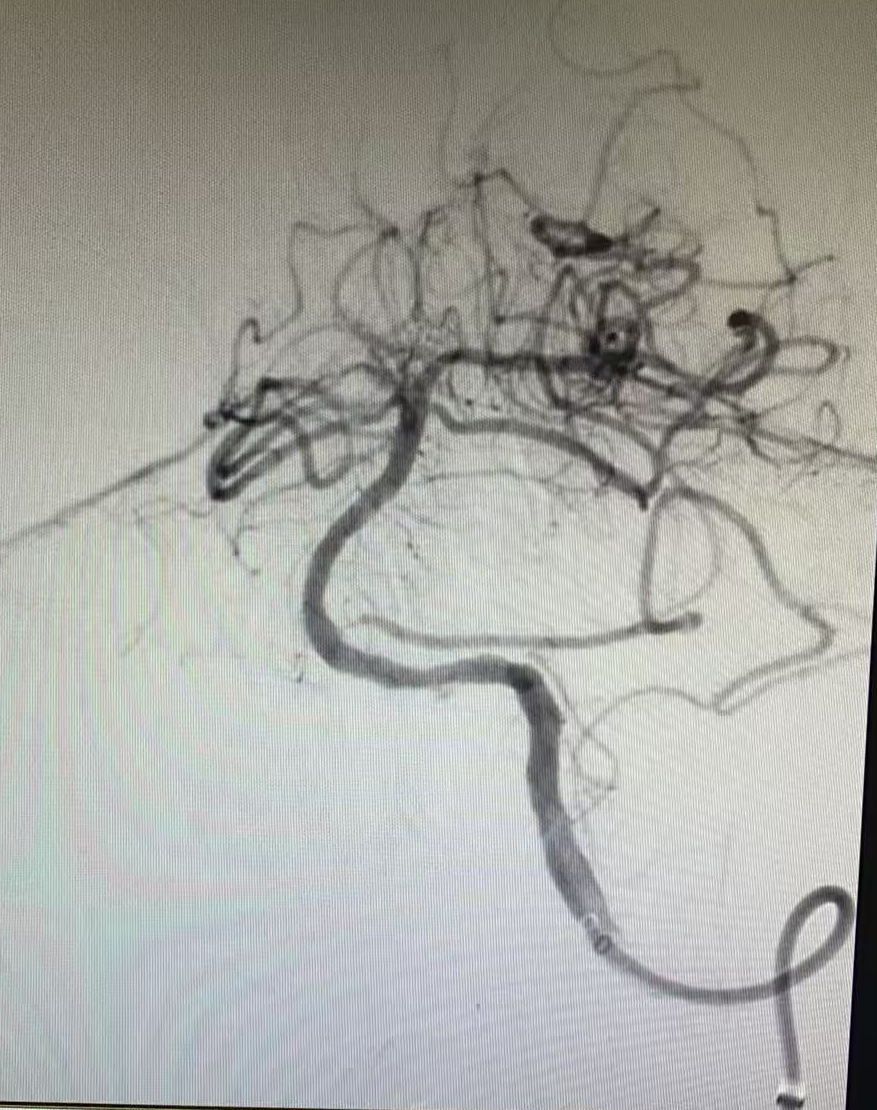

但挑戰(zhàn)還在繼續(xù),血管開通后發(fā)現(xiàn)內(nèi)部存在嚴(yán)重狹窄,遠(yuǎn)端血流灌注不足,團(tuán)隊隨即進(jìn)行球囊擴(kuò)張改善血流,但血管回縮明顯。為確保持久通暢,團(tuán)隊果斷植入一枚支架。最終,血管形態(tài)恢復(fù)良好,血流達(dá)到最佳標(biāo)準(zhǔn),缺血的大腦獲得了充足的血液供應(yīng)。

支架置入后

一場集腦動脈造影、顱內(nèi)動脈取栓、球囊擴(kuò)張與支架置入于一體的多模態(tài)手術(shù)順利完成。

成功的手術(shù)為患者贏得了寶貴的康復(fù)機(jī)會。術(shù)后第二天,郝先生就恢復(fù)了清醒,順利拔除了氣管插管,僅感到輕微頭暈,檢查未見明顯異常。復(fù)查顯示支架位置理想,血管通暢。